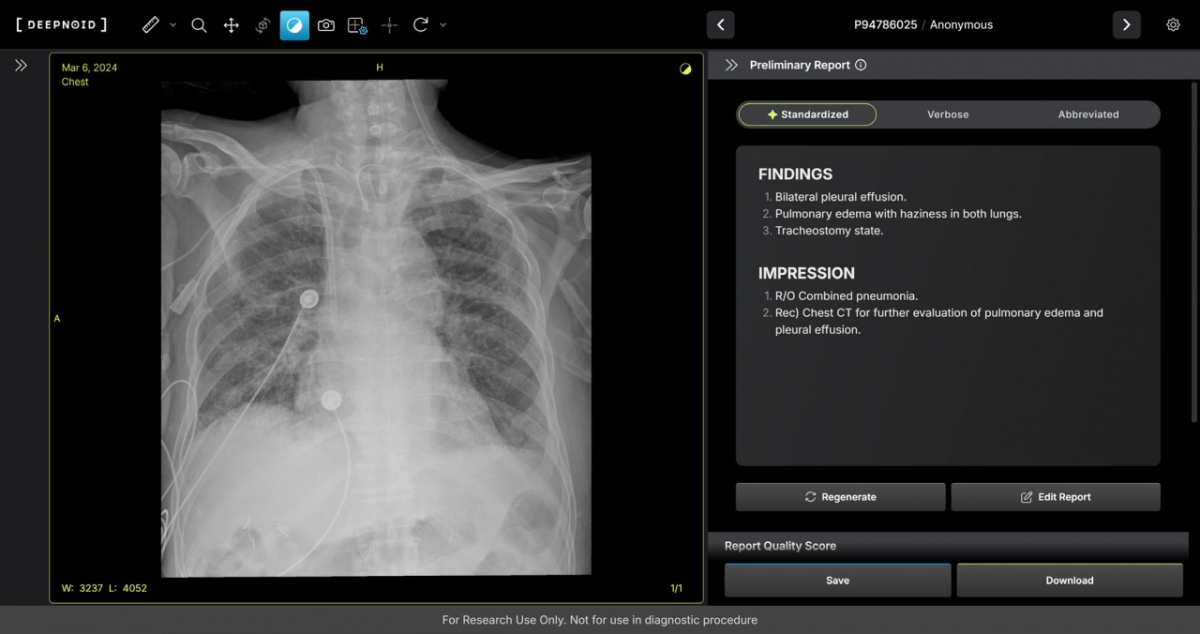

M4CXR은 흉부 엑스레이 영상에서 41종의 병변을 판독해 수초 만에 일관성 있고 신뢰성 높은 판독소견서 초안을 작성한다. 여기에는 흉부 엑스레이 영상과 대응되는 1000만건 이상의 판독소견서 데이터를 학습해 구현된 기술이 적용됐다. 특히 응급상황에서 의료진이 즉시 예비 판독 결과를 받을 수 있어 중요한 임상 결정과 환자 진료에 더욱 집중할 수 있도록 지원하며 영상의학과 전문의의 판독을 보조한다.

김성현 휴먼영상의학센터 원장은 "흉부 엑스레이는 임상 현장에서 가장 빈번하게 시행되는 검사이지만, 판독 의사의 부족으로 판독 속도에 한계가 있었다"며 "증가하는 영상 판독 수요 속에서 응급상황에서도 의뢰와 동시에 예비 판독 결과를 의료진에게 전달할 수 있어 진단의 신속성을 높이며, 영상의학과 전문의의 판독을 보조하여 정확성을 높이는 데 기여할 것으로 기대한다"고 말했다.